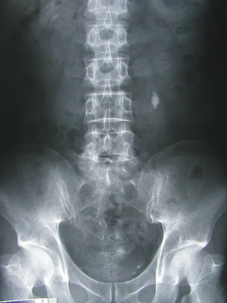

腎臟影像學檢查:包括X光檢查(來檢視腎臟的外觀、位置和大小,同時偵測腎結石的有無)及超音波掃描(透過此檢查可以得知腎臟是否萎縮、是否有腎結石、腎腫瘤、多囊性腎臟、腎髓質鈣化或腎盂水腫等)

腹部X光檢查